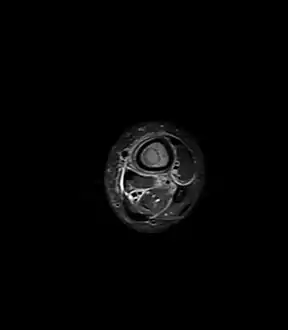

Oval, elliptical, or serpentine radiolucency usually greater than 1 cm surrounded by a heavily reactive sclerosis, granulation tissue, and a nidus often less than 1 cm. The margins often appear scalloped on radiograph. Brodie's abscess is best visualized using computed tomography (CT) scan. Associated atrophy of soft tissue near the site of infection and shortening of the affected bone. Osteoblastoma may be a classic sign for Brodie's abscess.